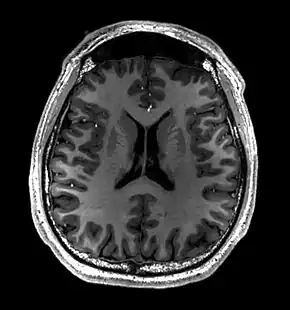

Brain regions on T1 MRI

T1 (note CSF is dark) with contrast (arrow pointing to meningioma of the falx)

- T1-weighted (T1W) images: Cerebrospinal fluid is dark. T1-weighted images are useful for visualizing normal anatomy.